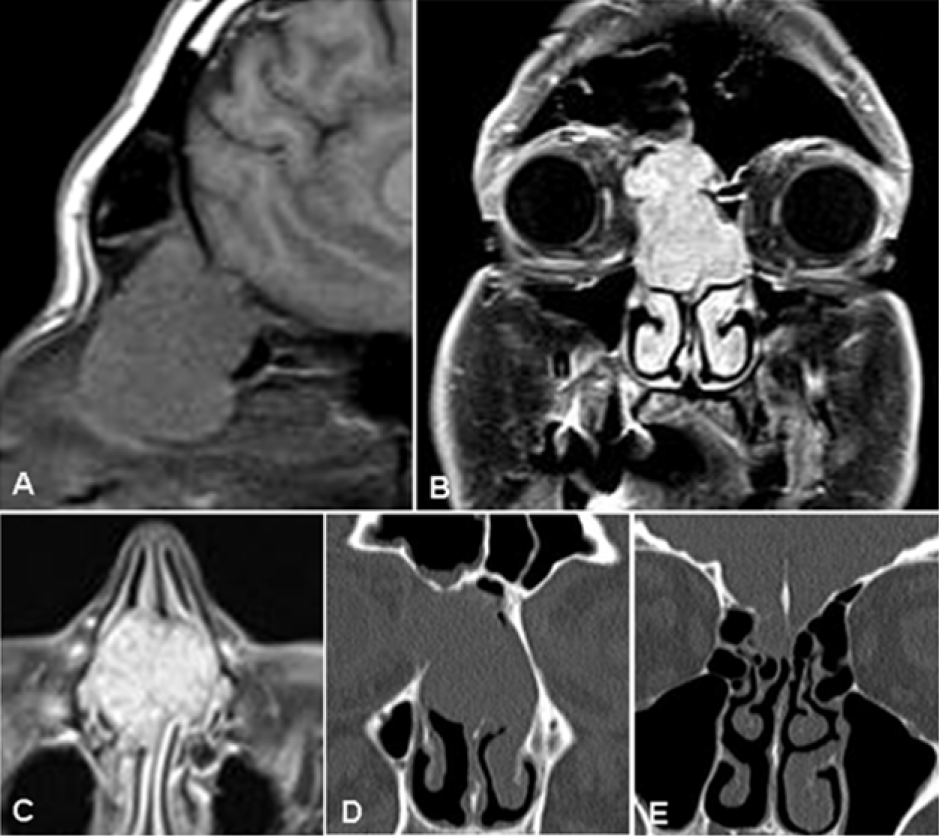

| Figure 1: MR/CT diagnostic work-up. Solid mass showed hypointense signal on sagittal T1 weighted images (A) with net and homogeneous enhancement after intravenous administration of gadolinium contrast agent on coronal (B) and axial (C) planes. CT images (D and E) demonstrated bone remodelling of the cribriform lamina and the medial wall of the right orbit. |